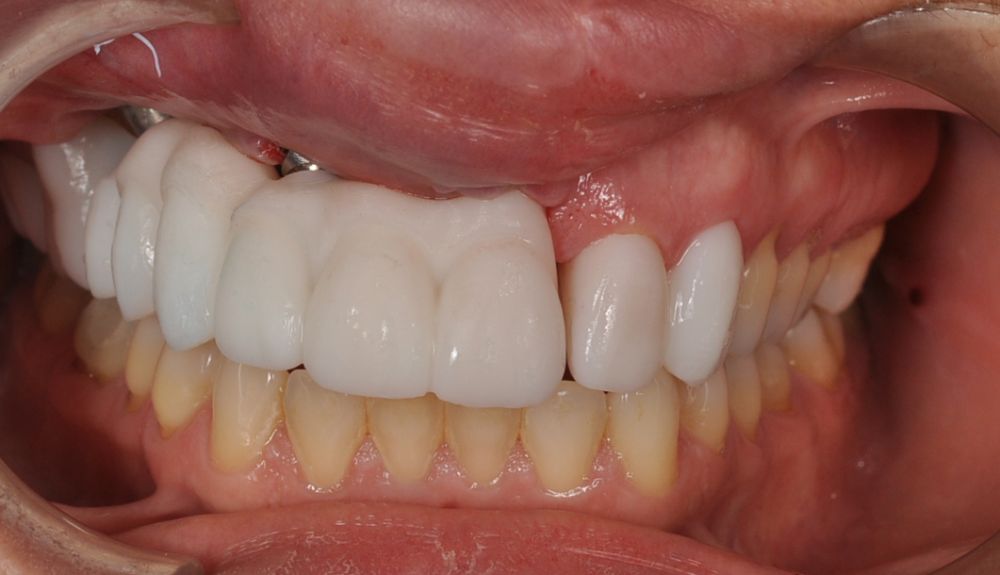

El día de la colocación de las estructuras, se arenó el interior de las coronas dentosoportadas con óxido de aluminio de 50 m y fueron cementadas con cemento de resina Multilink Ò. El puente implantosoportado se atornilló al torque indicado (20Nw) (Figuras 14, 15, 16 y 17).

Las impresiones analógicas y el posterior flujo digital permitieron una correcta planificación protésica. Las estructuras definitivas, confeccionadas en óxido de zirconio monolítico sobre interfases metálicas de titanio, mostraron una adecuada adaptación pasiva tanto clínica como radiográficamente. La prueba estética permitió ajustes oclusales y funcionales mínimos, optimizando el resultado final.

En enero de 2021, el puente implantosoportado fue atornillado con un torque controlado (20 Nw), y las coronas dentosoportadas cementadas con éxito. La paciente refirió una notable mejoría en la función masticatoria, fonación y estética facial, manifestando un alto grado de satisfacción.

En el seguimiento a 4 años tras la colocación de la prótesis definitiva, no se observaron complicaciones mecánicas ni biológicas. La paciente continúa libre de enfermedad y con una correcta adaptación al tratamiento rehabilitador implantosoportado (Figura 18).